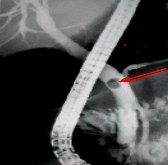

(五)、消化道狭窄扩张术、支架置入术

对于消化道各种消化道恶性狭窄,如食管癌、贲门癌、十二指肠癌及结肠癌等,均可在消化科行内镜下或“X”线下扩张或同时行支架置入术可有效解除梗阻,恢复进食,明显改善生存质量。